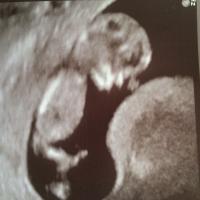

week scan tomorrow 😍

14.03.2018